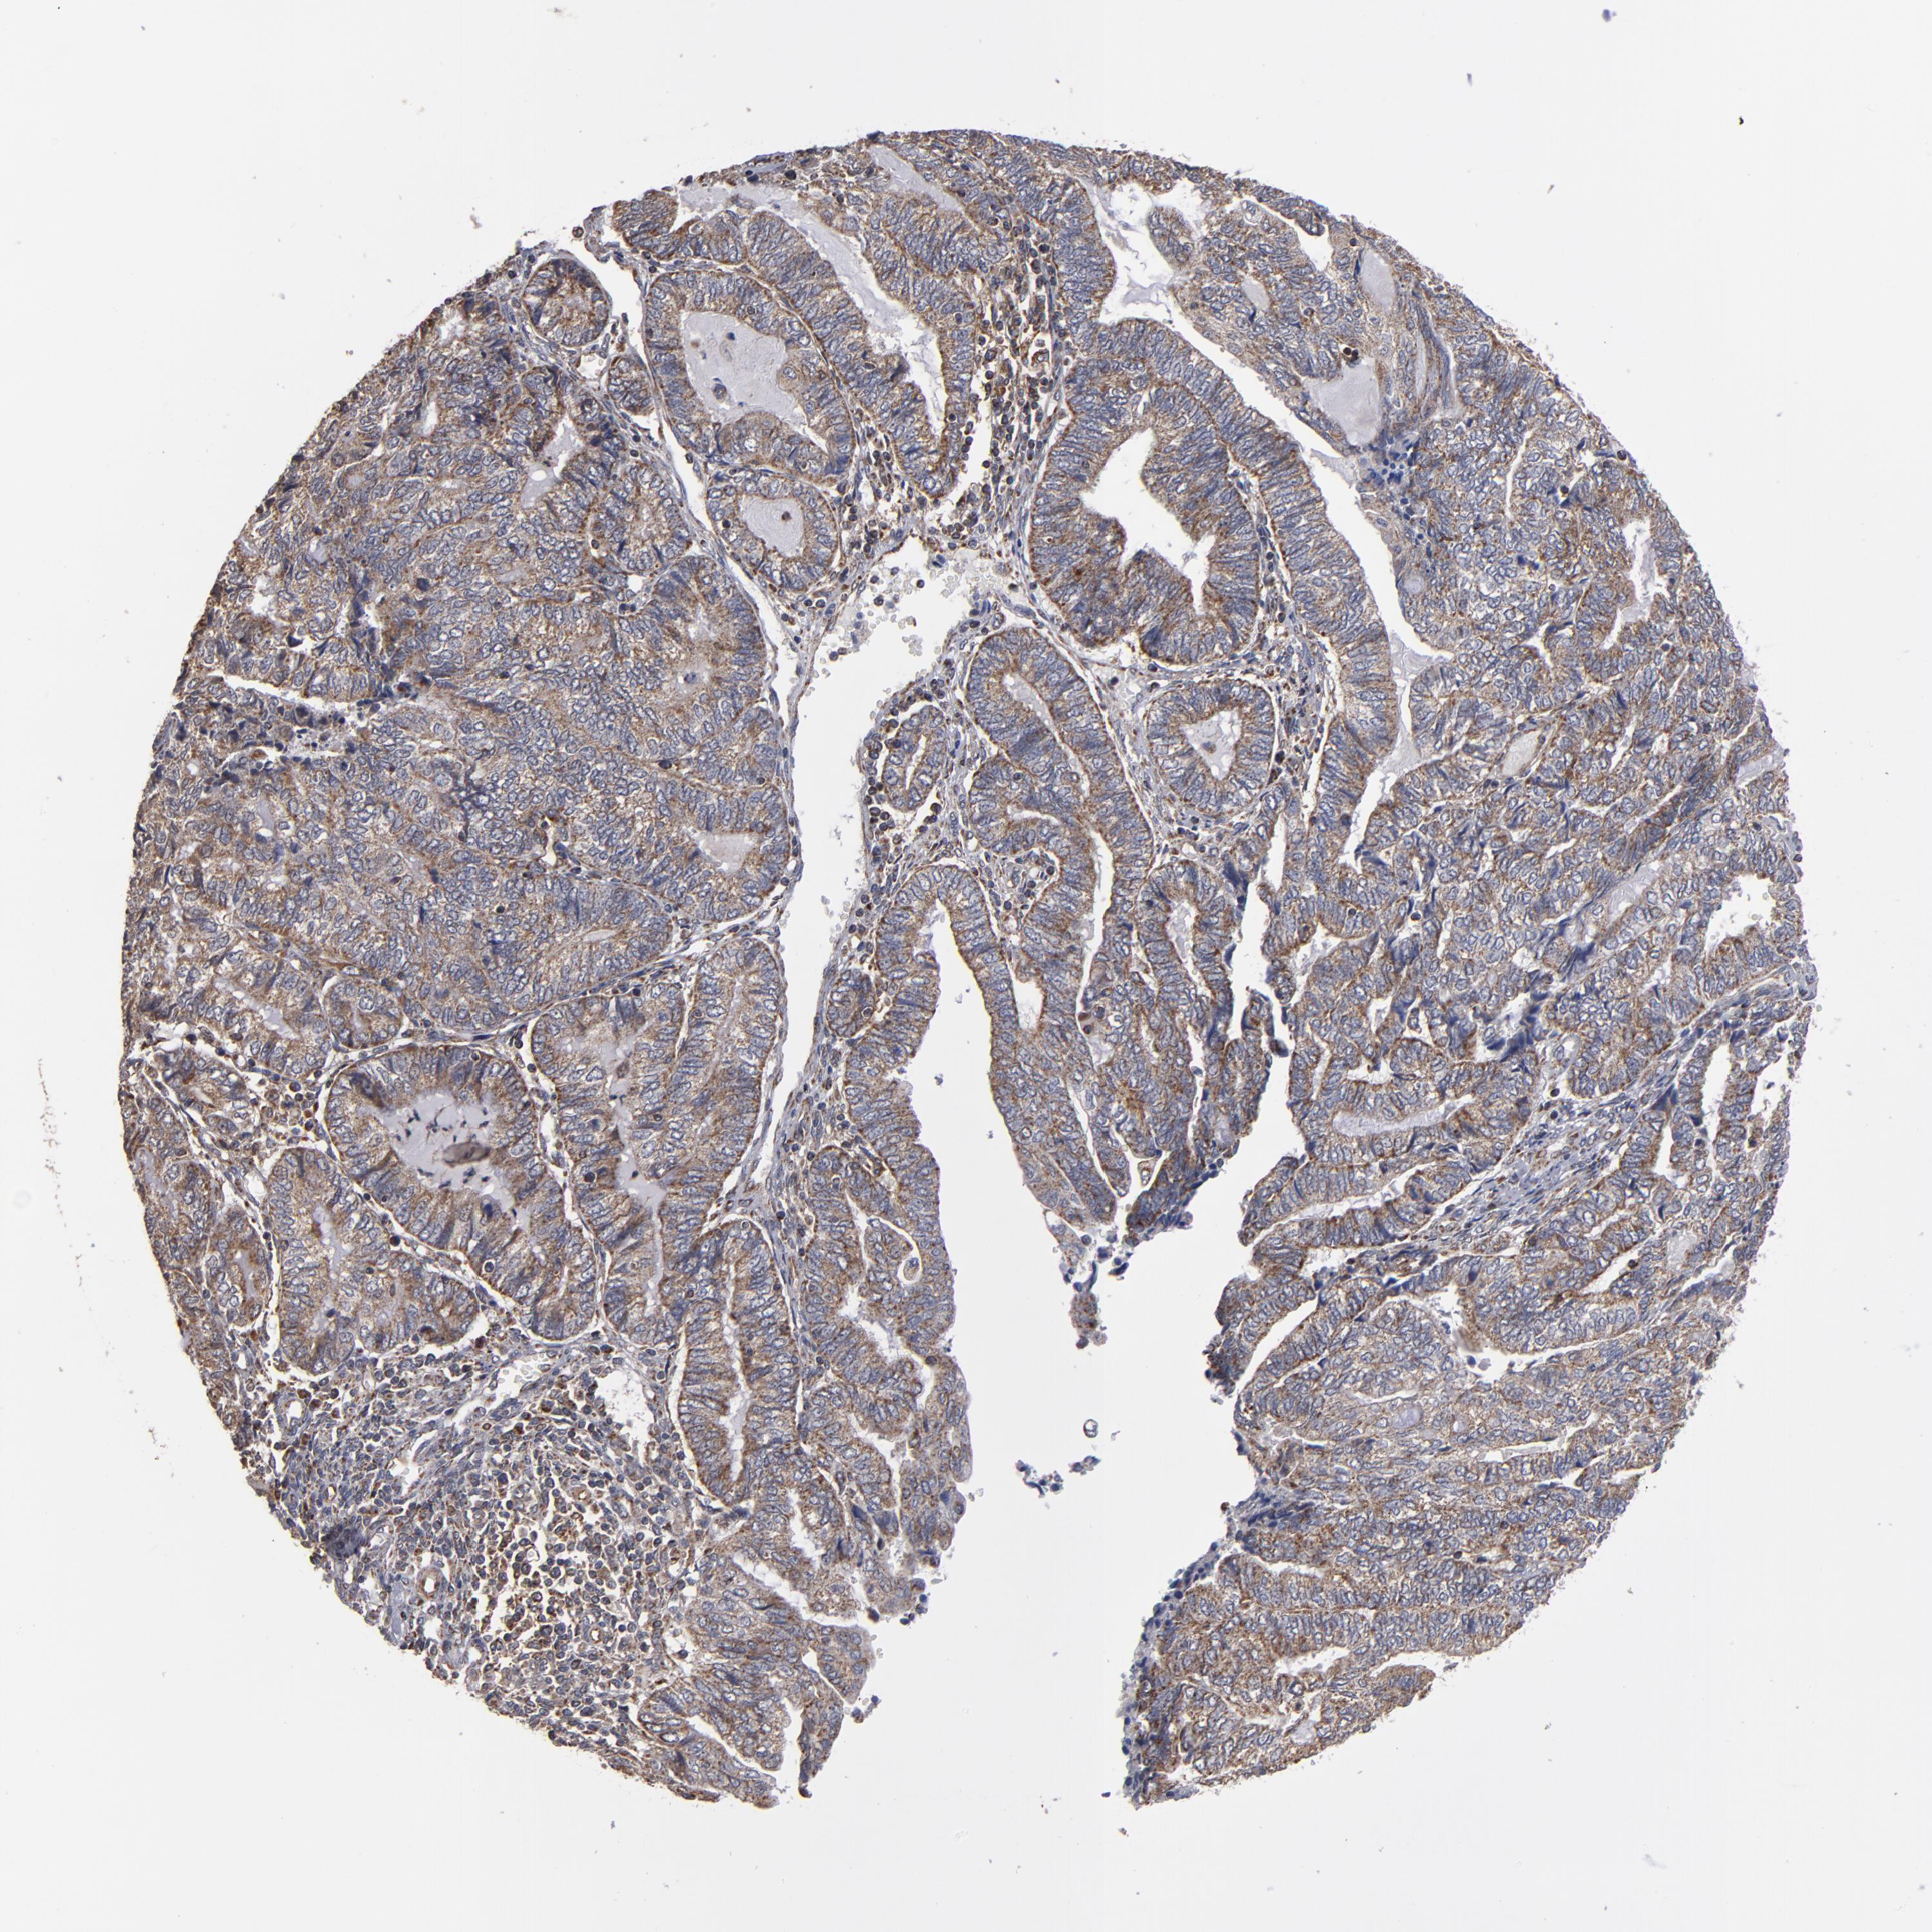

ENDOMETRIAL CANCER - Protein expressioni

A mouse-over function shows sample information and annotation data. Click on an image to view it in a full screen mode. Samples can be filtered based on level of antibody staining by selecting one or several of the following categories: high, medium, low and not detected. The assay and annotation is described here.

Note that samples used for immunohistochemistry by the Human Protein Atlas do not correspond to samples in the TCGA dataset.

Antibody stainingi

Antibody staining in the annotated cell types in the current human tissue is reported as not detected, low, medium, or high, based on conventional immunohistochemistry profiling in selected tissues. This score is based on the combination of the staining intensity and fraction of stained cells.

Each image is clickable and will lead to virtual microscopy that enables deeper exploration of all samples and also displays staining intensity scores, fraction scores and subcellular localization as well as patient and tissue information for each sample.

Antibody HPA002893

Staining

High

Medium

Low

Not detected

Intensity

Strong

Moderate

Weak

Negative

Quantity

>75%

75%-25%

<25%

None

Location

Nuclear

Cytoplasmic/membranous

Cytoplasmic/membranous,nuclear

Adenocarcinoma, NOS

Neoplasm, malignant, NOS